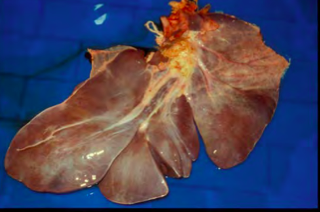

Capsular hepatic fibrosis. Equine liver.

Capsular fibrosis/perihepatitis filamentosa and atrophy of right liver lobe in a horse with colonic impaction.